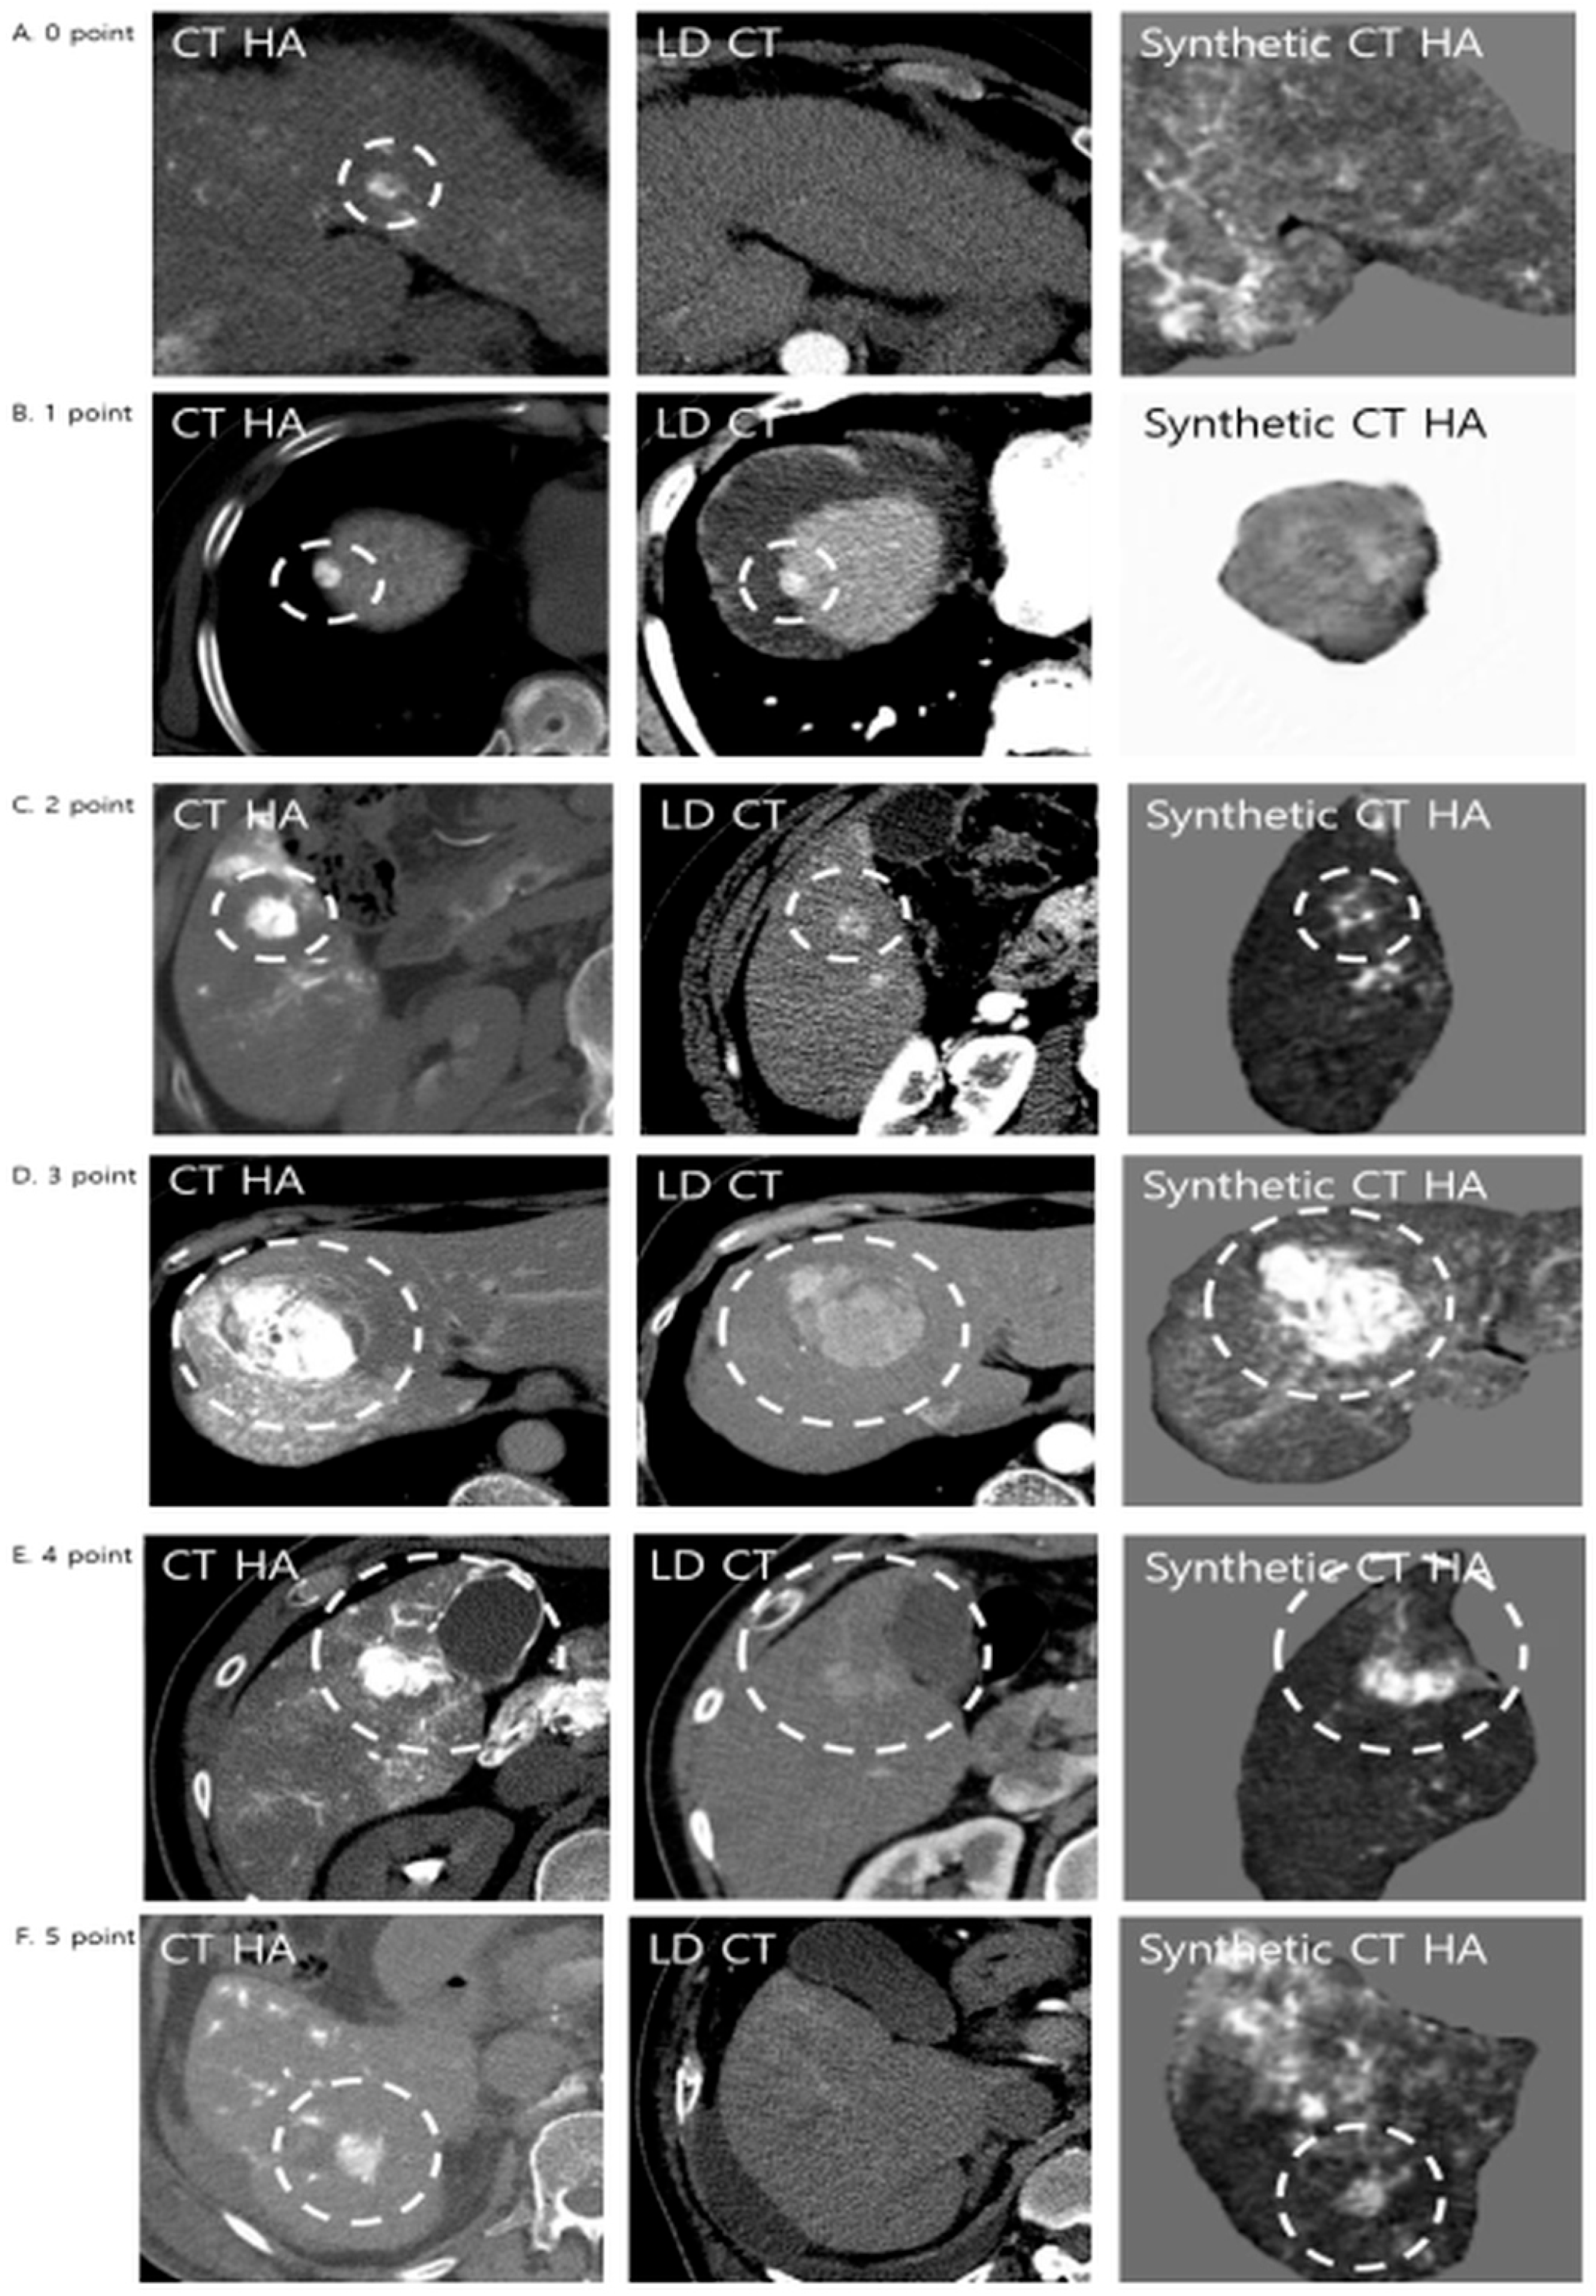

Qualitative assessment comprised three distinct components. First, lesion conspicuity was quantified using a three-point visual grading scale: grade 1 denoted lesions that were not visible; grade 2 indicated lesions visible only upon adjusting window settings; and grade 3 represented lesions clearly visible at standard settings. Second, the comparative detection value of the synthetic images relative to LDCT was evaluated using a five-point Likert scale (Figure 3). In this hierarchy, score 0 indicated that the lesion was invisible on both modalities, while scores 1 and 2 reflected instances where the synthetic image was inferior to the LDCT (lesion lost or lower quality). A score of 3 denoted an equivalent detection value. Conversely, scores 4 and 5 represented superior detection value, with score 5 specifically highlighting “occult” lesions—those invisible on LDCT but successfully visualized on synthetic CTHA. Finally, lesion detection rates were stratified by tumor diameter (<1 cm, 1–2 cm, and ≥2 cm) to assess size-dependent sensitivity.

Figure 3. Representative examples of diagnostic performance comparing LDCT and Synthetic CTHA. Lesions were evaluated using a 5-point diagnostic value score. The white dashed circles indicate the hypervascular lesions. (A) Score 0: The lesion is invisible on both LDCT and Synthetic CTHA. (B) Score 1: The lesion is clearly visible on LDCT but lost on Synthetic CTHA (inferior). (C) Score 2: The lesion is visible on Synthetic CTHA but with inferior quality compared to LDCT. (D) Score 3: The lesion shows equivalent conspicuity on both modalities. (E) Score 4 (Superior): The lesion is visible on LDCT, but Synthetic CTHA shows it more clearly with higher contrast. (F) Score 5 (Significantly Superior): The lesion is subtle or invisible on LDCT but is clearly visualized on Synthetic CTHA, demonstrating the potential for detecting occult HCCs.